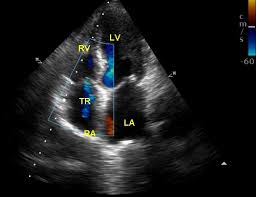

Van 3 lá nằm giữa nhĩ phải và thất phải. Khi tim co bóp, van đóng để máu đi về phía động mạch phổi. Nếu có một dòng máu phụt ngược về nhĩ phải, siêu âm Doppler sẽ ghi nhận trào ngược van ba lá.

Từ sinh lý thường dùng khi dòng phụt ngược rất nhỏ. Thời gian phụt ngắn. Không kèm giãn buồng tim, tim to hay dấu suy tim thai. Nói cách khác, đó là dấu hiệu quan sát được, chưa phải chẩn đoán bệnh.

Điểm quan trọng là mức độ và bối cảnh. Trào ngược nhẹ, đơn độc, tim cấu trúc bình thường thường có tiên lượng tốt. Ngược lại, trào ngược vừa hoặc nhiều, kèm dấu bất thường khác cần đánh giá chuyên sâu.